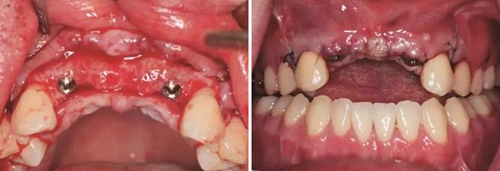

圖19 早期修復(fù)1月 圖20 早期修復(fù)2月

圖21 早期修復(fù)3月 圖22 早期修復(fù)3月打開三角間隙

圖23 早期修復(fù)4月 圖24 早期修復(fù)7月切除軟組織增生后

圖25 早期修復(fù)7月調(diào)改橋體部形態(tài)為卵圓形并高度拋光 圖26 早期修復(fù)8月